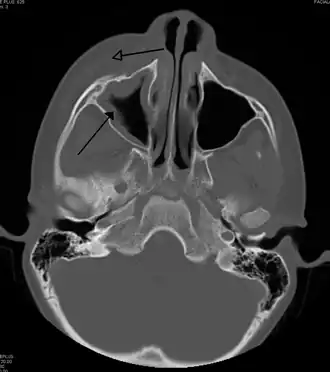

For cases of maxillary sinusitis, limited field CBCT imaging, as compared to periapical radiographs, improves the ability to detect the teeth as the sources for sinusitis. A coronal CT picture may also be useful.[60]

Maxillary sinusitis caused by a dental infection associated with periorbital cellulitis -